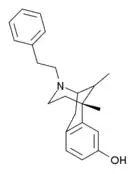

Morphinans

Morphinan series

- 3-Hydroxymorphinan

- 4-Chlorophenylpyridomorphinan

- Cyclorphan

- Levargorphan

- Levorphanol

- Levophenacylmorphan

- Levomethorphan

- Methorphan (racemethorphan)

- Morphanol (racemorphanol)

- Norlevorphanol

- N-Methylmorphinan

- Oxilorphan

- Phenomorphan

- Proxorphan

- Ro4-1539

- Stephodeline Xorphanol

Structures

| Other morphinans | ||||

|---|---|---|---|---|

4-chlorophenylpyridomorphinan 4-chlorophenylpyridomorphinan |

Cyclorphan Cyclorphan |

Dextrallorphan Dextrallorphan |

Levargorphan Levargorphan |

Levophenacylmorphan Levophenacylmorphan |

Levomethorphan Levomethorphan |

Norlevorphanol Norlevorphanol |

N-Methylmorphinan N-Methylmorphinan |

Oxilorphan Oxilorphan |

Phenomorphan Phenomorphan |

Dextromethorphan Dextromethorphan  levomethorphan levomethorphan |

Morphanol Morphanol |

Ro4-1539 Ro4-1539 |

Stephodeline Stephodeline |

Xorphanol Xorphanol |